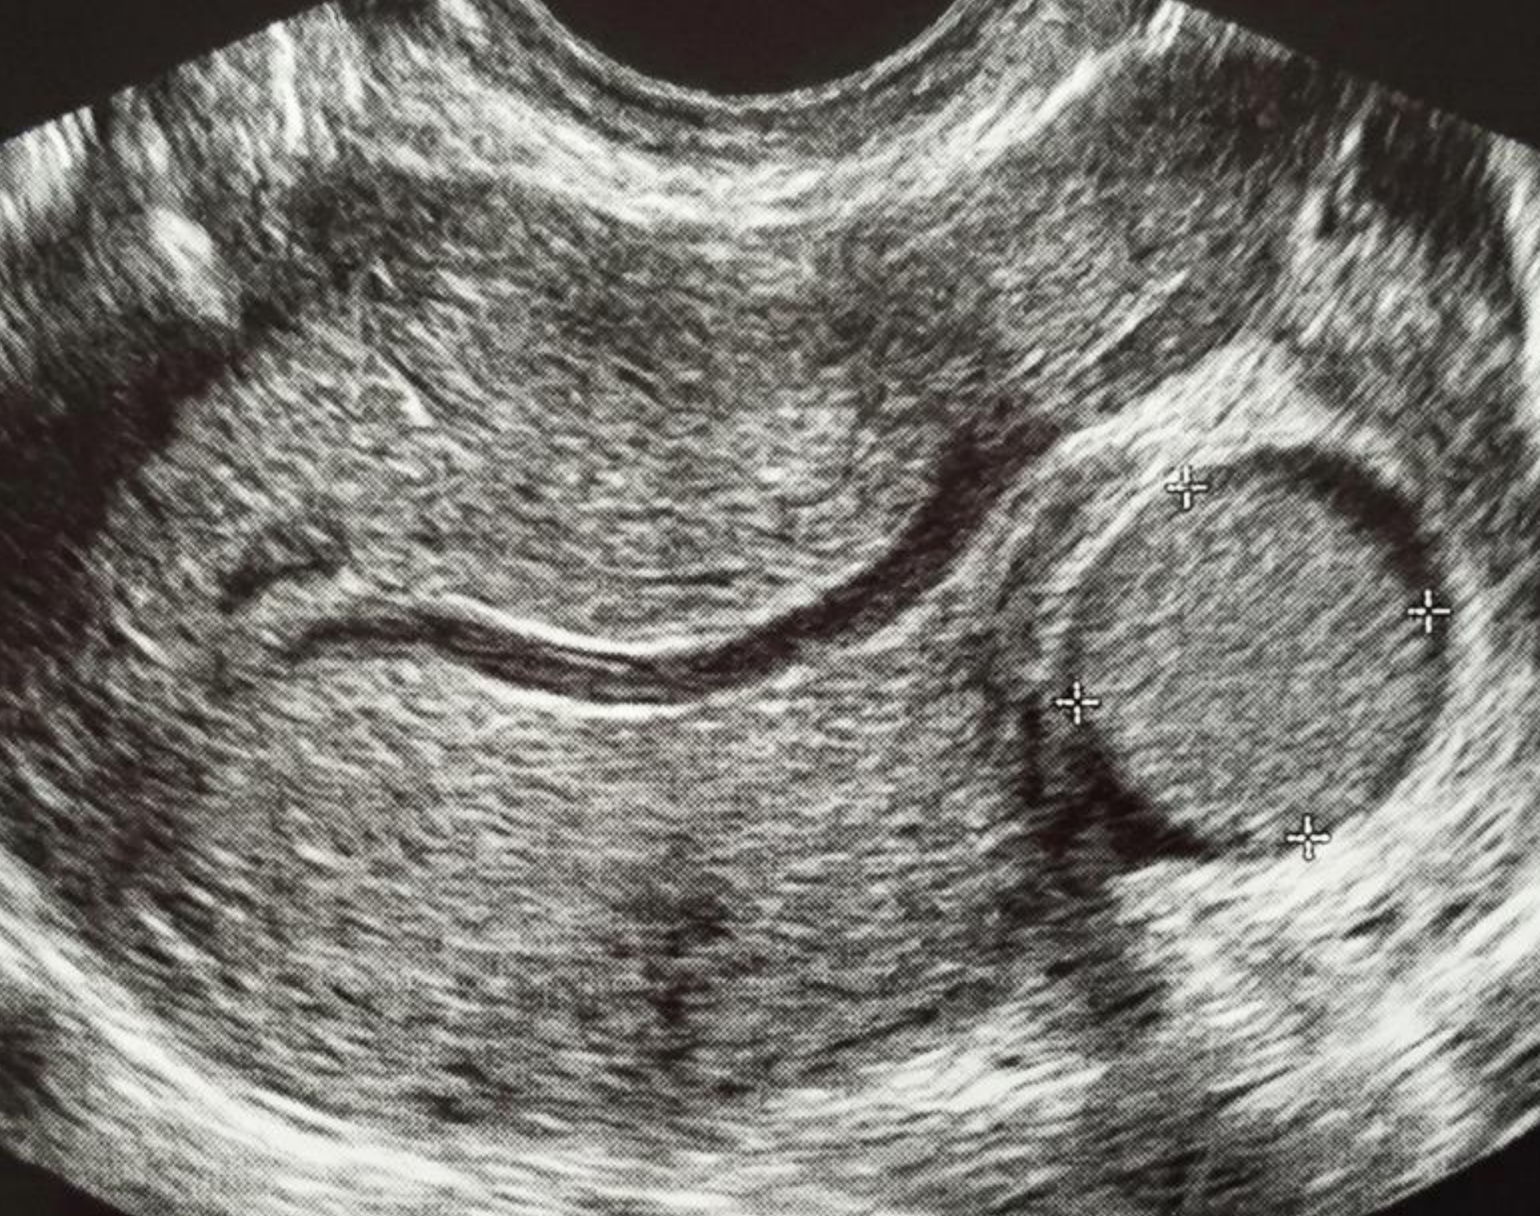

🖼️Exemplo de FIGO 7:

📋Descrição recomendada para o laudo de US:

Formação nodular miometrial compatível com mioma totalmente externa ao contorno uterino, sem componente intramiometrial, presa à serosa por pedículo.